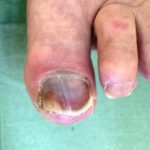

Ногти при сахарном диабете

Симптомы заболевания проявляются и в виде деформации пальцев и ногтей. Пальцы ног при диабете утолщаются, деформируются, на них появляются красные или синюшные пятна.

Характерный вид имеют ногти при сахарном диабете (на фото 6): они становятся ломкими, расслаиваются, часто врастают уголками в кожу. Часто в этом повинна присоединившаяся грибковая инфекция. Ломкость капилляров, особенно при тесной обуви, приводит к кровоизлияниям под ногтевой пластинкой, и ногти чернеют.